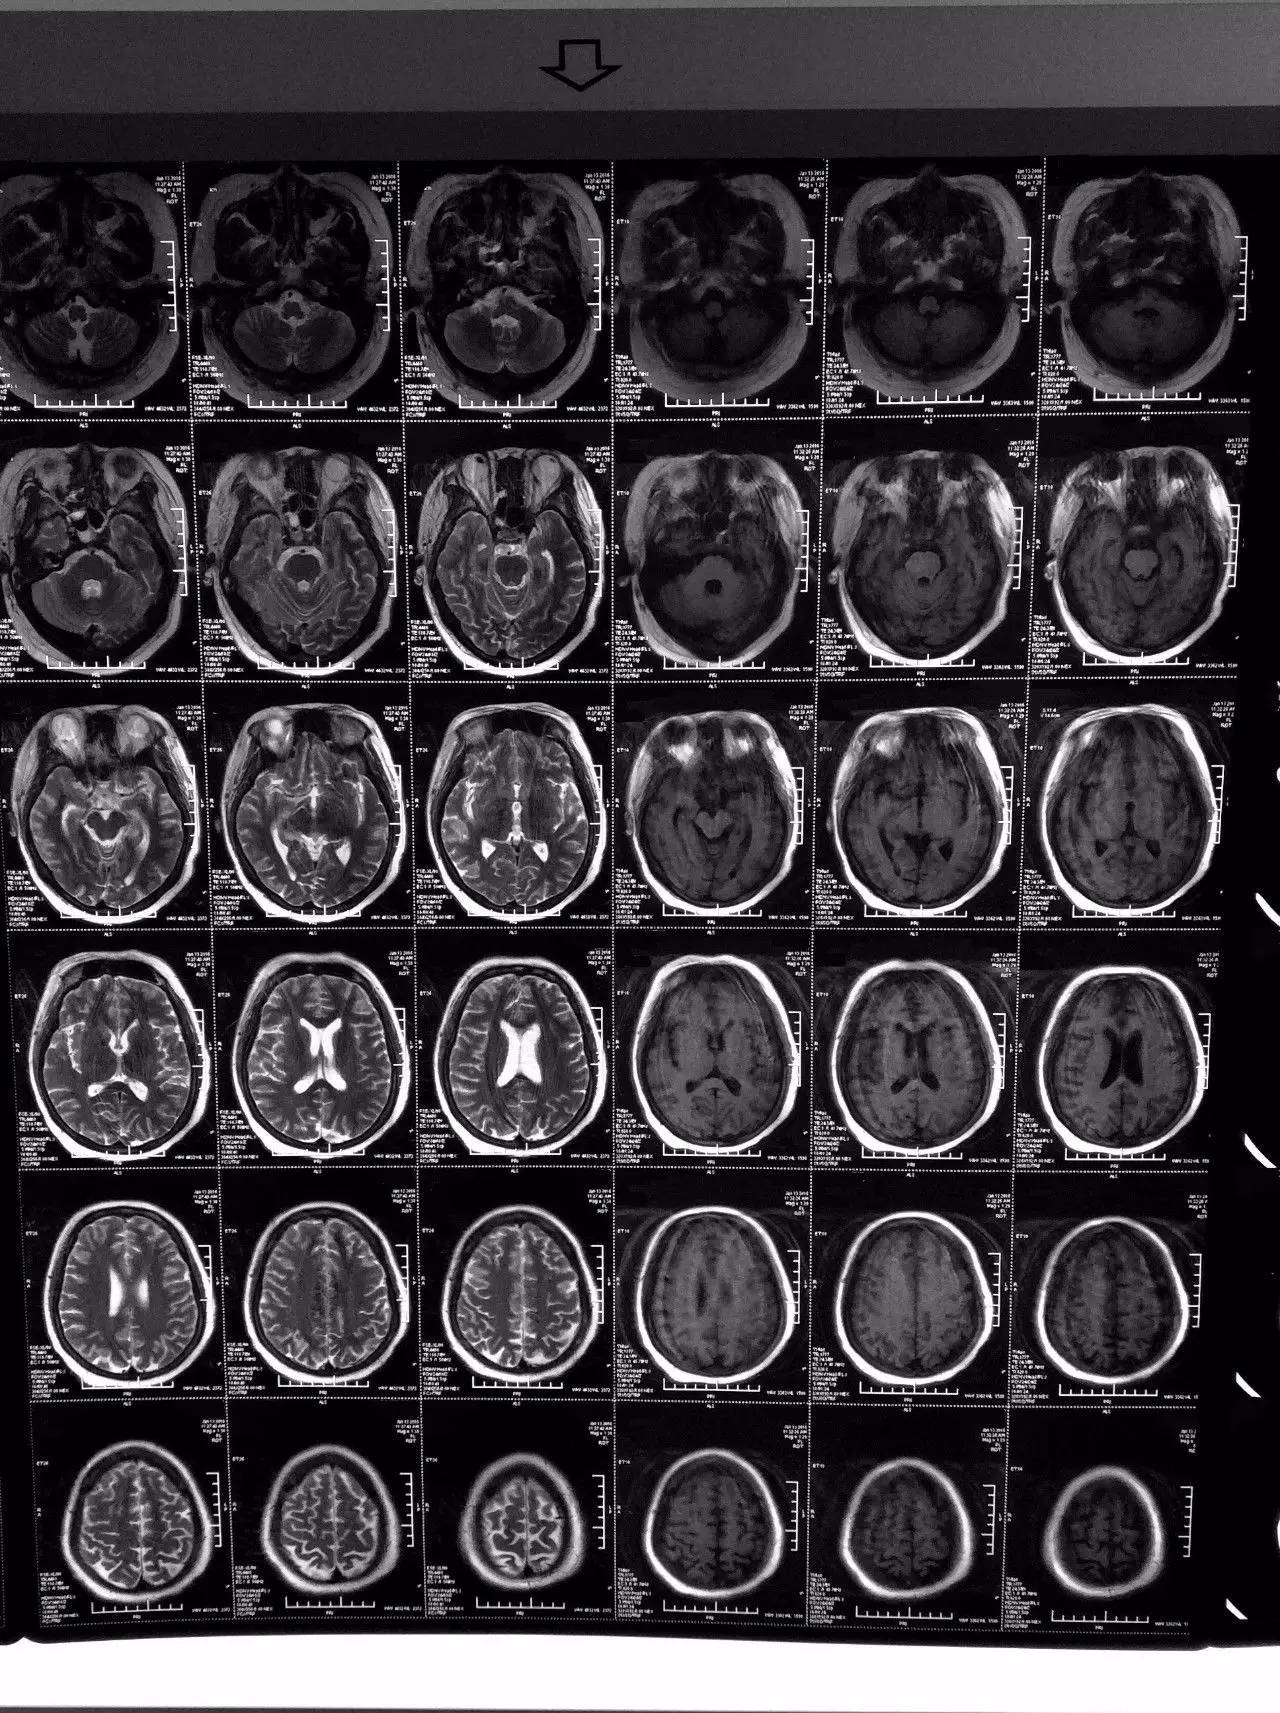

▼患者影像资料